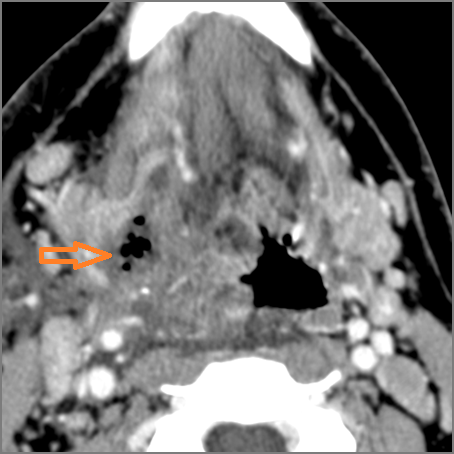

Vascular Findings

There is evidence of thrombus,thrombophlebitis or other occlusive or inflammatory process of the jugular vein or smaller venous tributaries.

There is evidence of thrombus, thrombophlebitis or other occlusive or inflammatory processsmaller jugular venous tributaries.